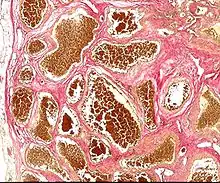

Histology of a cavernous hemangioma | |

Cerebral cavernous malformation (CCM) is a cavernous hemangioma that arises in the central nervous system. It can be considered to be a variant of hemangioma, and is characterized by grossly large dilated blood vessels and large vascular channels, less well circumscribed, and more involved with deep structures, with a single layer of endothelium and an absence of neuronal tissue within the lesions. These thinly walled vessels resemble sinusoidal cavities filled with stagnant blood. Blood vessels in patients with cerebral cavernous malformations (CCM) can range from a few millimeters to several centimeters in diameter. Most lesions occur in the brain, but any organ may be involved.[1]